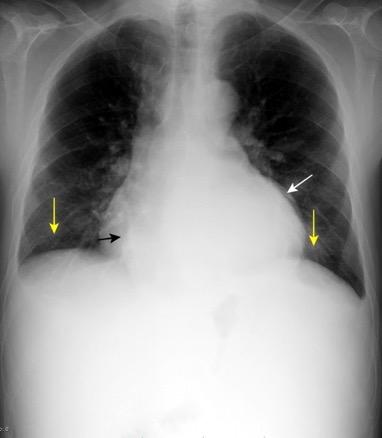

Parálisis frénica transitoria tras cirugía de válvula aórtica

Parálisis frénica transitoria post cirugía cardiaca (10%).

Puede acompañarse de atelectasia del LII.

Benjamin JJ et al. . Left lower lobe atelectasis and consolidation following cardiac surgery: the effect of topical cooling on the phrenic nerve. Radiology 1982